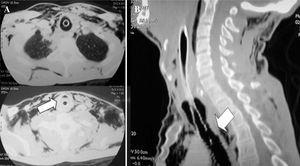

Fig. 3. Tomografía computarizada (TC) cervicotorácica del caso 1, que presentaba una lesión traqueal por arma blanca. A: cortes de TC, donde la flecha señala el nivel hidroaéreo intratraqueal. Gran enfisema mediastínico y subcutáneo. Drenaje torácico por neumotórax. B: reconstrucción de TC cervical, con flecha que señala la lesión traqueal cervical.